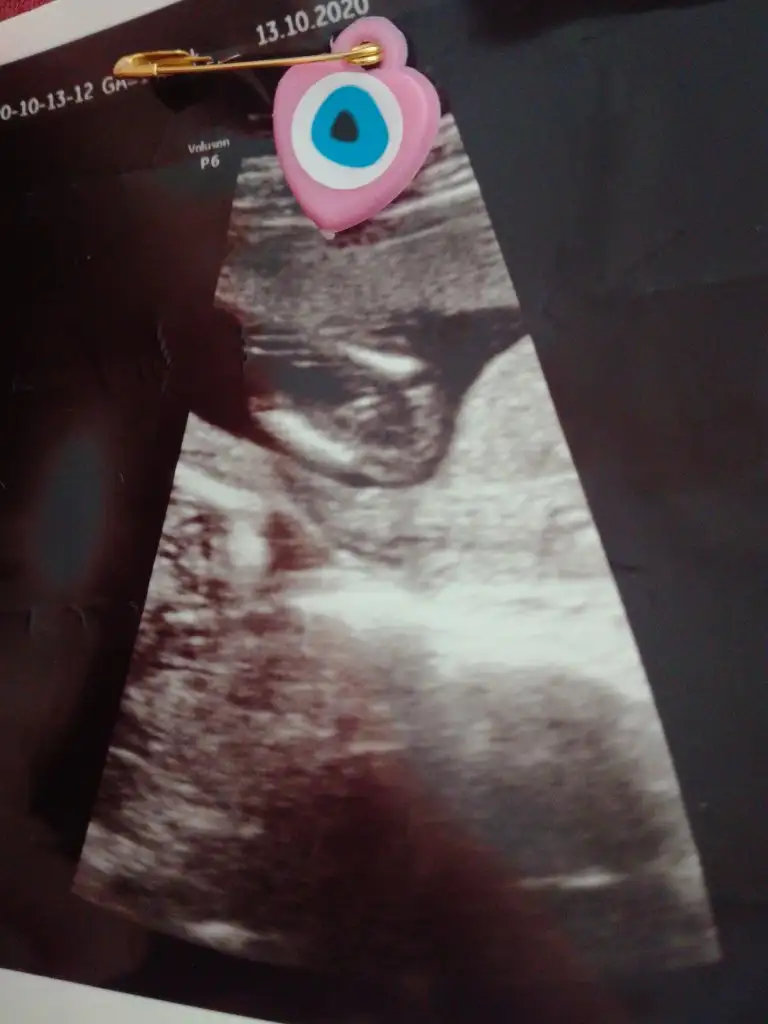

Canım şimdi sen benimkine muz da olabilir erkek de kararsızım diyorsun anladığım kadarıyla Doktorumuz gibiBana bu USG paylasmadiniz ki burada karşıya bakıyor nubu %60 erkek olabilir derim bu bunlar yanitir ayrıca Dr gibi detaylı bakmıyorum Dr verdiği çıktıysa göre tahmin ediyorum ama senin bebeğin kafa şekli kizada yatkın

Evet olma ihtimali varCanım şimdi sen benimkine muz da olabilir erkek de kararsızım diyorsun anladığım kadarıyla Doktorumuz gibine nubu varmış bizimkinin çözebilene aşk olsun

Evet ikisi kız gibi sankiAmin ininşaallahvalla hiç poz vermediler hep kapattılar ama doktor ikisinde de çengel falan dedi sanırım cinsiyet kısımları bunlar ben hiç bişey anlamıyorum ama attım bugün tam 14hafta bitti